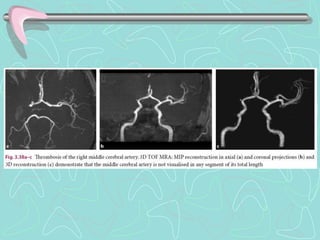

ARTERIOGRAFÍA DE CAROTIDAS

•Técnica invasiva, con uso de contraste

•Detecta obstrucción de vasos sanguíneos (Ictus isquémico)